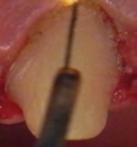

Figura 1. Aparato de radiofrecuencia Ellman Surgitron FFPF EMC, EE. UU. Figura 2. Diferentes puntas para radiofreciencia. Puntas de tungsteno. Figura 3. Punta de trabajo en contacto con el tejido.

Para realizar el desplazamiento gingival se seleccionó en onda parcialmente rectificada (coagulación), potencia baja (2), y se conectó la punta de trabajo en fulguración. El pedal se activó solo cuando la punta de trabajo estuvo muy cerca del contacto con el tejido.

Se pasó la punta seleccionada, únicamente en contacto con el tejido blando cerca del surco gingival en cada pilar preparado (Figura 3). Cuando la punta se encontró en contacto con el tejido, se mantuvo en movimiento constante para evitar el calor excesivo; el movimiento fue en una sola dirección. En el caso del desplazamiento gingival, el diente se tomó como guía para el electrodo.